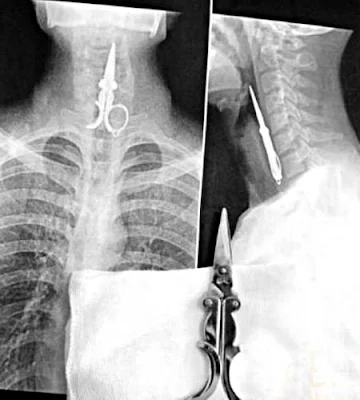

Swallowed the pair of scissors shown in the bottom of the picture.